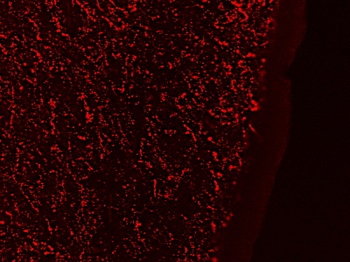

| Tested Applications | IHC |

| Dilution Range | IHC: 1/10-1/50; ELISA: 1/5000-1/10000 |

| Reactivity | Human |

| Target | PROKR2 |